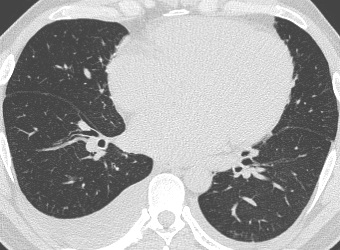

SARS-CoV-2 CT Scan dataset [50]: The dataset was collected from hospitals of Sao Paulo, Brazil, with a total of 2482 CT scans acquired from 120 patients of both genders. It is composed of 1252 scans for patients infected with SARS-CoV-2 and 1230 scans for patients infected with other lung diseases. The CT scans have varying spatial sizes between and , and are available in PNG format. CT scans from this dataset are shown in Figure 7.

COVID19-CT dataset [51]: The dataset consists of a total of 746 CT images. There are 349 CT images of patients with COVID-19 and 397 CT images showing Non-COVID-19, but other pulmonary diseases. The positive CT images were collected from preprints about COVID-19 on medRxiv and bioRxiv, and they feature various manifestations of COVID-19. Since the CT images were taken from different sources, they have varying sizes between and . Figure 8 shows example CT images from the COVID19-CT dataset.